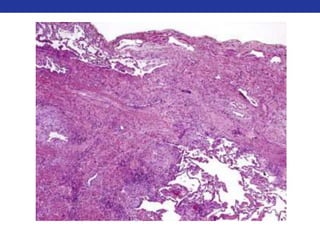

• Microscopic features

• Biphasic: Admixture of epithelial and stromal elements

• Epithelium: Glands or cords of small cuboidal cells

• Stroma: Fibromyxoid +/- cartilaginous differentiation

• Prognosis

• Vast majority are benign, Recurrence rate is highly dependent on adequacy of original resection

• Malignant transformation: Occurs in ~5% of cases